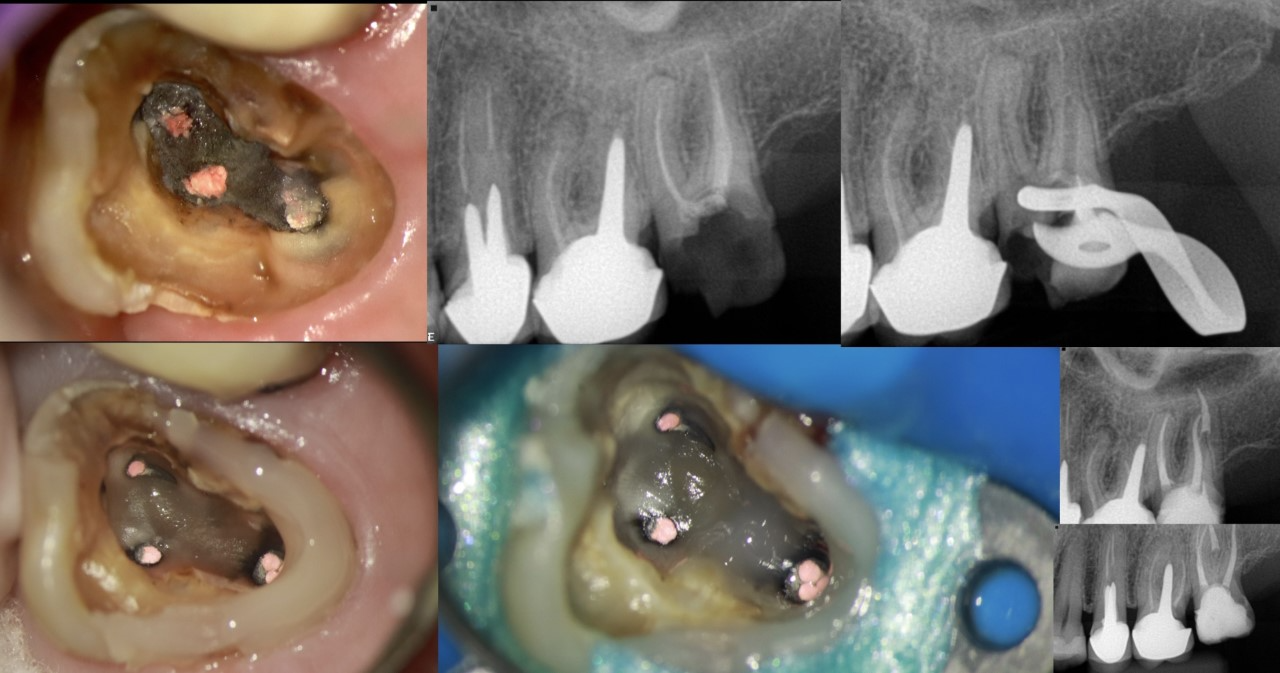

3. Uso de um adesivo autocondicionante BeautiBond Xtreme, pois este adesivo pode ser usado nas três técnicas de adesividade: total etching, self-etching e selective etching. Aplicação por esfregaço por 20 segundos, jogar ar por 10 segundos e fotopolimerização por 5 segundos. Você pode também usar em dentina outro qualquer adesivo autocondicionante. Caso você tenha esmalte no preparo, faça o condicionamento ácido somente no esmalte.

4. Aplicação da Resina Beautifil Flow Plus 00 circundando às margens do dente. Você eventualmente pode necessitar de uma matriz metálica para inserção desta resina em área interproximal.

5. Essa resina possui um escoamento mais grosso, o que facilita sua aplicação, pois onde você a coloca ela se estabiliza e fica. Após a colocação da resina, fotopolimerize por 10 segundos.

6. Você pode erguer as paredes na altura que precisar com esta resina, fazendo inserção em camadas.

7. Instale o grampo de isolamento diretamente na resina. Está resina sustenta um grampo sem ele expulsar.

8. Faça os procedimentos endodônticos que você necessitar fazer e você irá conseguir perceber a estabilidade do grampo durante todo o procedimento endodôntico que for executar (figuras 1 e 2).